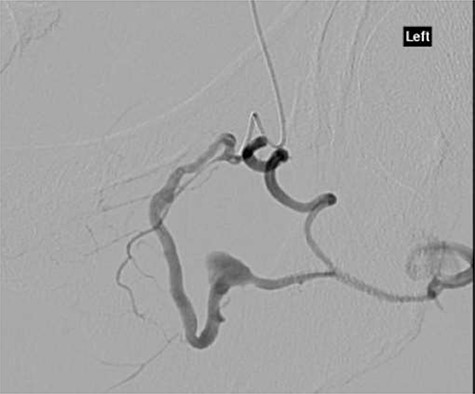

CT angiography showed multiple hypertrophied branches of the left internal iliac artery with heavy collateralisation to the territory of occluded left common femoral artery. Pathological dilatation of the collateral branch of the left obturator artery was identified as source of bleeding and embolized (Fig. 2). A further source of bleeding from a collateral muscular branch of the internal iliac artery was also embolized (Fig. 3).

CT angiography showing extravasation of dye from muscular branch of the internal iliac artery (black arrow).